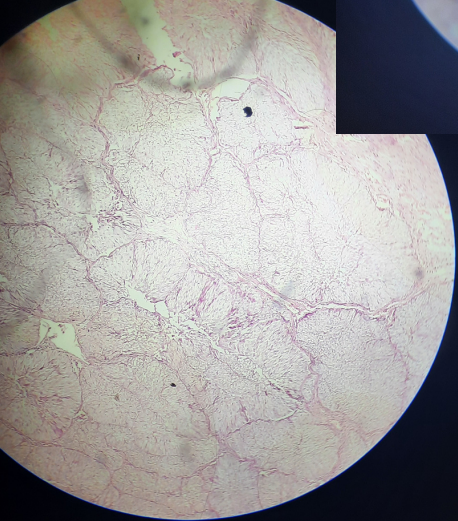

5

Benign prostatic hyperplasia

Proliferation of both the acini and the fibromuscular stroma